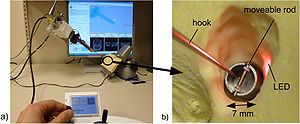

- 7.10 Distance Measurement in Middle Ear Surgery using a Telemanipulator